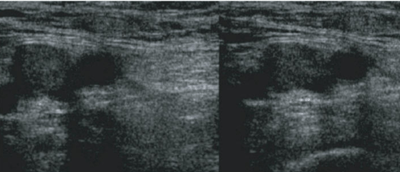

- Each segment of vein identified must be assess as compressible and noncompressible

- Touching of the anterior and posterior walls indicates a normal exam

- No touching with pressures sufficient to deform the artery indicates DVT

Normal

- Arteries are the thick walled and more circular vessels identified

- Lymph nodes may be confused with noncompressible vein and if found, can be identified by moving up or down 1 cm

- An appropriate amount of pressure gives complete collapse of the vein as well as some (but not full) compression of the adjacent artery.[3]